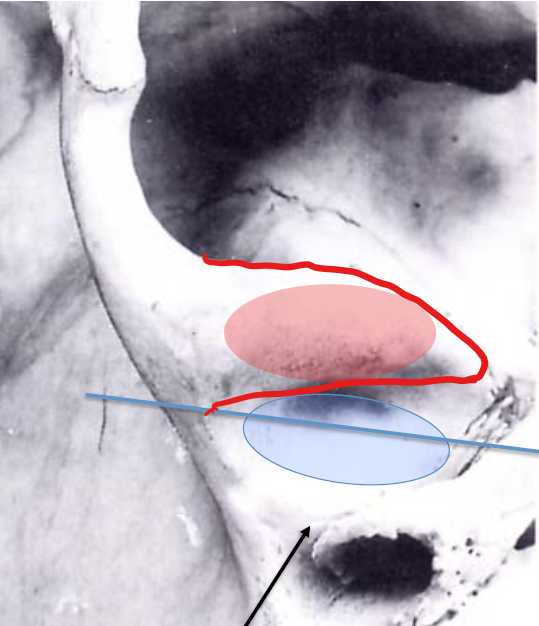

Coucouuuu je te met ce schéma où c'est plus visible !

La fosse est une sorte de dépression alors que le tubercule est une convexité, la fosse est en arrière (post) concave en ventral et en avant, le tubercule articulaire est en avant (ventral) convexe en arrière et en bas !

Je t'ai représenté le tubercule articulaire et la fosse mandibulaire sur un schéma en coupe transverse (schéma 1) et en coupe sagittale (schéma 2).

Le tubercule articulaire c'est un relief osseux limitant la fosse mandibulaire en avant, c'est une structure appartenant à l'os temporal (Cf. cours du Dr. De Barros), il est recouvert de cartilage et s'articule avec le processus condylaire du ramus mandibulaire lors des mouvements de l'ATM.

La fosse mandibulaire elle, est simplement une dépression entre la racine longitudinale et transverse (le tubercule articulaire) de l'os temporal (encore une fois Cf. cours du Dr. De Barros) dans laquelle se loge le condyle mandibulaire, elle est principalement recouverte d'une membrane synoviale.